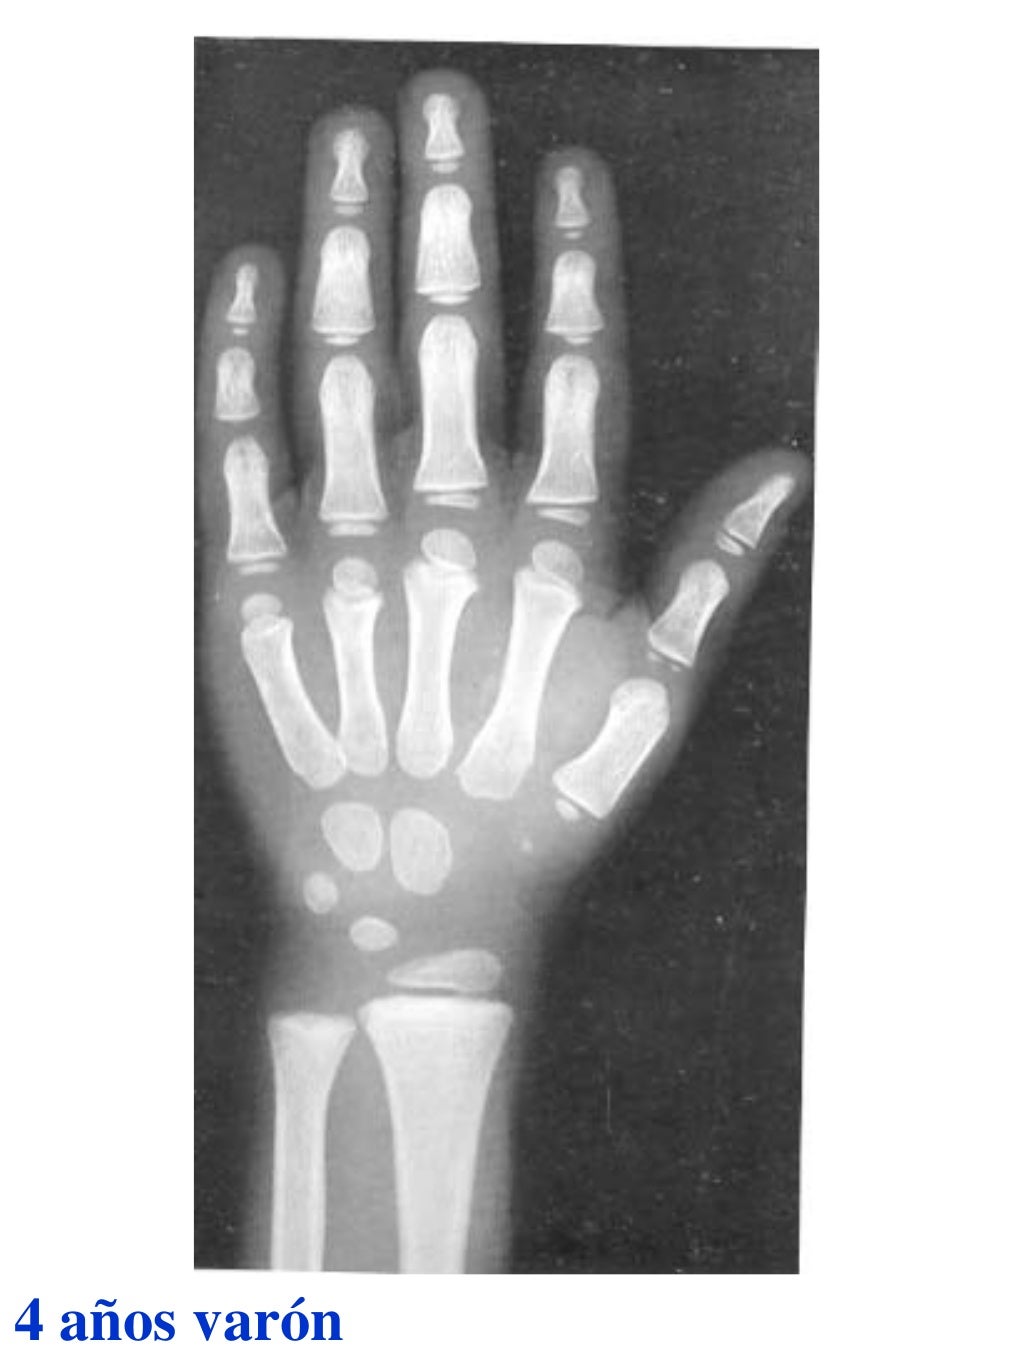

Figura 2 Imágenes de radiografías de mano y muñeca izquierda del

Figura 2 Imágenes de radiografías de mano y muñeca izquierda del Tablas De Greulich Y Pyle Edad Osea The greulich and pyle atlas is used to estimate the age of children and adolescents. El método de greulich y pyle(1) es un método simple de valoración de la edad ósea en pacientes pediátricos. El diagnóstico y la clasificación se basan en el examen físico, el análisis del crecimiento, la maduración ósea, la ecografía de útero y gónadas, y los. Tablas De Greulich Y Pyle Edad Osea.